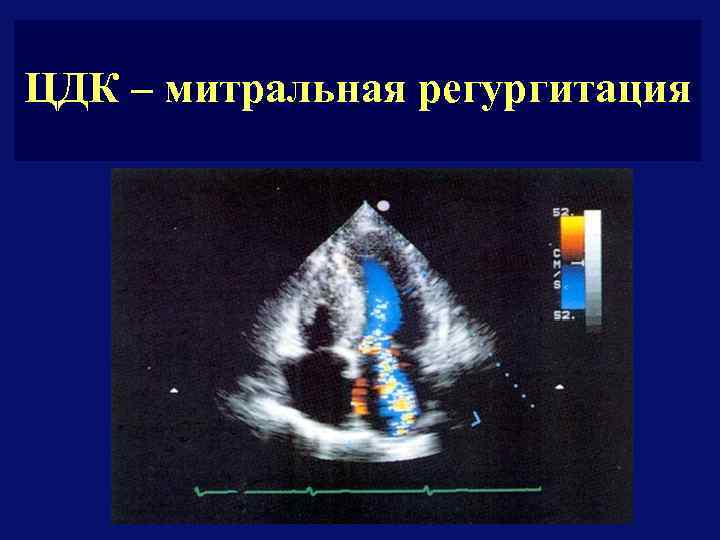

ЦДК – митральная регургитация